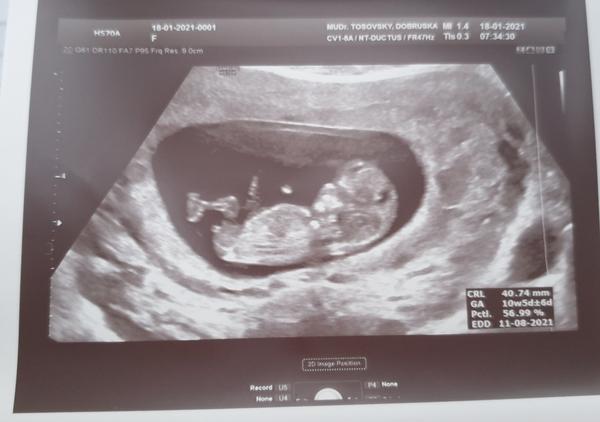

Pohlaví miminka 13.tt. Změnilo se pak ještě?

Ahoj holky, byla jsem na svém prvním screeningu a Doktor řekl že to bude kluk, stalo se to některé z vás,a byla z toho nakonec holčička? Předem moc děkuji za odpověď